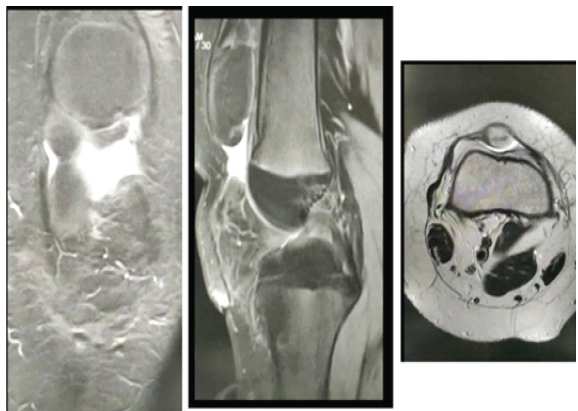

Magnetic resonance imaging of the right knee showed a complete tear of the patellar tendon with inflammatory changes in the Hoffman pad of fat and minimal fluid in the infrapatellar region. The patella was displaced superiorly, suggesting Grade-1 medial collateral injury (Fig. 3).

Figure 3: Magnetic resonance images, coronal, sagittal, and axial views.